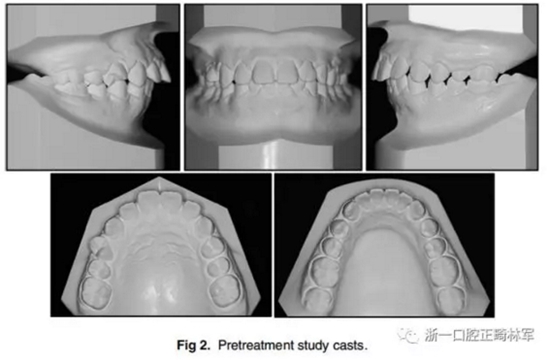

1.口內(nèi)像(Fig 1)、研究模型(Fig 2)和全景X光片(Fig 3)顯示了輕度牙列間隙,覆牙合覆蓋較大,右上第一前磨牙扭轉(zhuǎn)。覆牙合為4.0 mm,覆蓋為5.5 mm,兩側(cè)有輕微的Ⅱ類磨牙關(guān)系。除了上頜第二磨牙以外的所有牙齒都已經(jīng)萌出,患者口腔衛(wèi)生不良,有廣泛的牙齦炎癥,但牙槽骨未吸收。顳下頜關(guān)節(jié)形態(tài)良好,沒有癥狀。